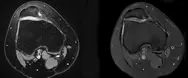

Aleris ortopædkirurg Lars Blønd har udviklet en operation kaldet ”The arthroscopic deepening trochleoplasty” (ADT). Det er en teknik, hvor operationen for løs knæskal udføres med kikkertteknik. Kikkertoperationen er mere skånsom for knæet. Derved er der færre smerter og mindre ar, og patienten kommer sig hurtigere.

Det er en operation der anvendes, når furen til knæskallen er flad, og det giver problemer med løs knæskal eller kroniske forreste smerter. Ved Trokleaplastik-operationen får du skabt en dybere fure til knæskallen, hvis denne mangler eller ikke er dyb nok. Er din fure til knæskallen i den øverste del af knæet for flad, har du det som kaldes Trochlear Dysplasi.